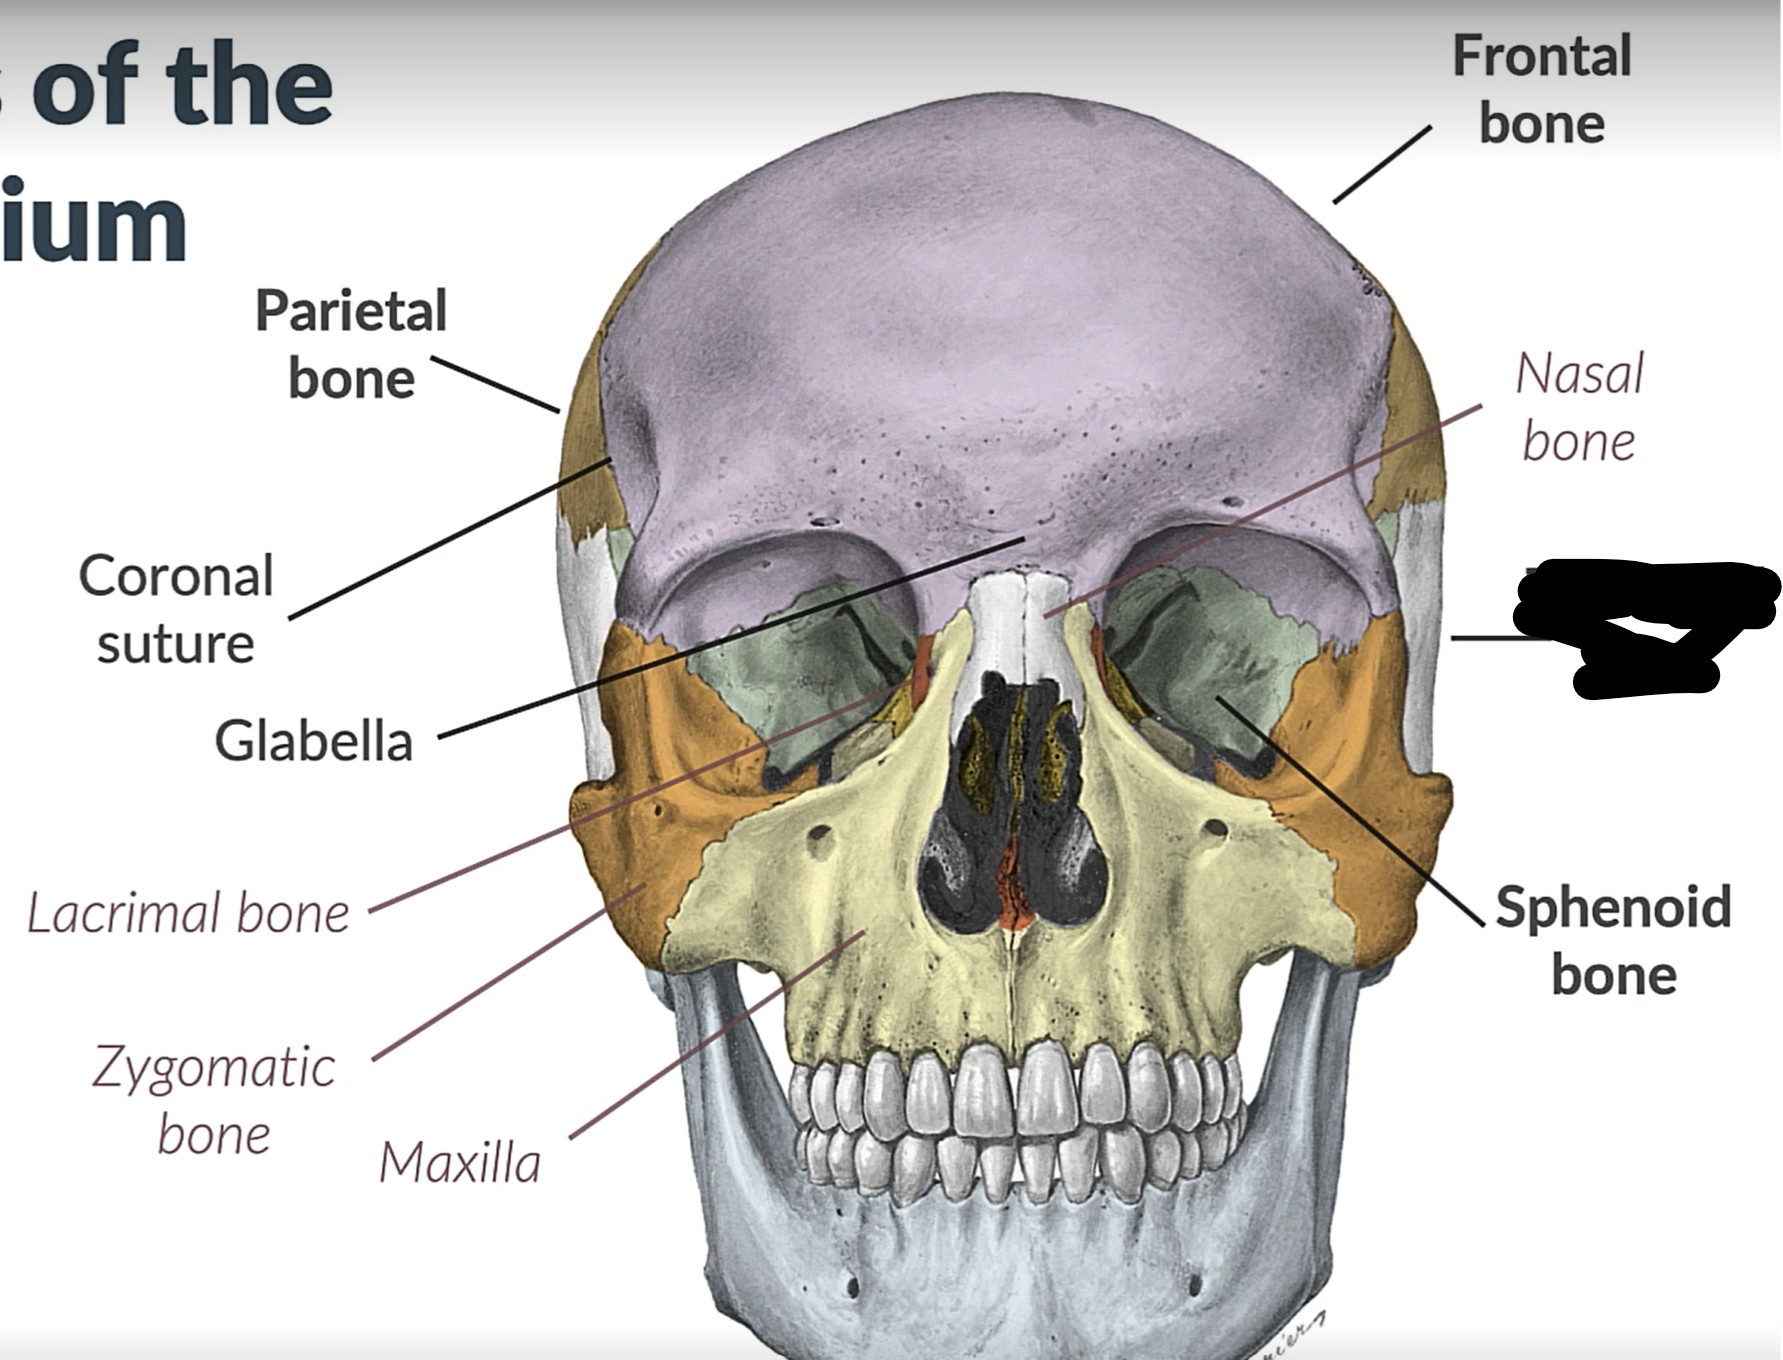

Parietal bone

Frontal bone

Temporal bone

Sphenoid bone

Zygomatic bone

Lacrimal bone

Coronal suture

Maxilla